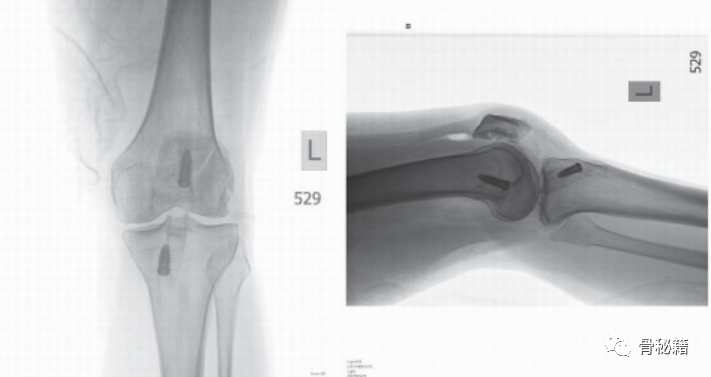

术后影像

同样,该患者有粉碎型和垂直型骨折,用钢板、螺钉和骨移植物固定以恢复关节面

坚强固定,小的钢板或多枚的克氏针结合来达到较好的固定效果